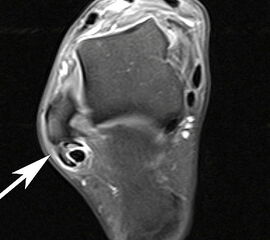

MRT mit KM bei Split der Peronaeus brevis Sehne in Höhe der Fibulaspitze

Abbildung 13

Klassischerweise beginnt eine Peronealsehnenruptur mit einem Distorsionstrauma. Bei dieser Verletzung kommt es zunächst zu einer Längsruptur (Peroneus-Split) der Peronaeus brevis Sehne in Höhe der Fibulaspitze. Bestehen nun Risikofaktoren wie eine persistierende Instabilität des Sprunggelenks oder ein bis zu diesem Zeitpunkt asymptomatischer Rückfußvarus, kommt bei jeder weiteren Distorsion zu einer Zunahme des Sehnenschadens bis hin zur vollständigen Kontinuitätsunterbrechung 38. Für das Peronaeus Split Syndrom gibt es kein klassisches Leitsymptom. Wichtig ist bei anhaltenden Beschwerden nach einem Distorsionstrauma an diese Differentialdiagnose zu denken und ein MRT mit Kontrastmittel zu veranlassen 39.